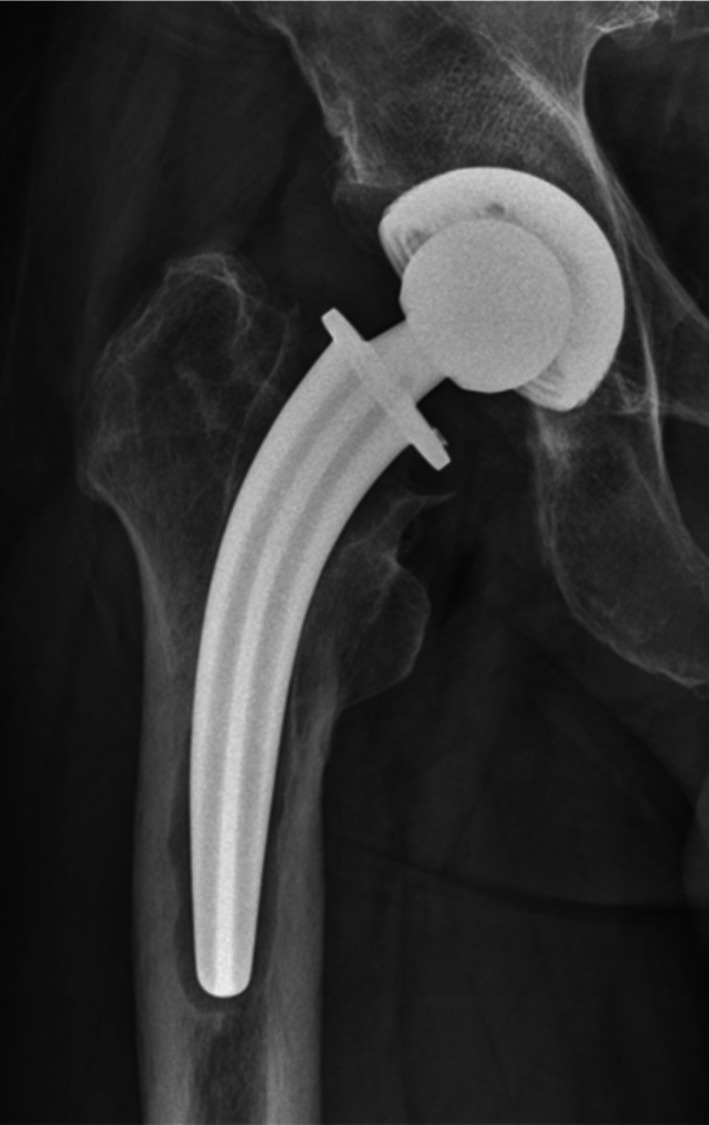

Objective: The Collum Femoris Preserving (CFP) stem offers biomechanical advantages in total hip arthroplasty (THA). However, aseptic loosening remains the most common cause of failure and other severe complications, with specific risk factors associated with the CFP stem remaining inadequately defined. This study aims to investigate the possible factors associated with aseptic loosening.

Methods: This study retrospectively analyzed patients who underwent primary THA with the CFP stem from January 2004 to December 2009 in our institution. Patients were divided into two groups based on whether there was aseptic loosening. Demographic and imaging parameters were collected from medical records and the hospital's Picture Archiving and Communication System (PACS). Comparative analyses were conducted, and variables with significant differences were subjected to Cox regression to identify independent risk factors of aseptic loosening.

Results: A total of 469 hips were included, with 52 hips (11.1%) of aseptic loosening identified. Seven independent risk (protective) factors were found, including ceramic-on-polyethylene (COP) bearing surfaces (Hazard Ratio = 2.084, 95% Confidence Interval: 1.043-4.166, p = 0.038), history of steroid therapy (HR = 2.393, 95% CI: 1.056-5.425, p = 0.037), neck resorption ratio (NRR) (HR = 1.019, 95% CI: 1.005-1.033, p = 0.008), bone mineral density (BMD) (HR = 0.933, 95% CI: 0.891-0.976, p = 0.003), canal fill ratio (CFR) (HR = 0.951, 95% CI: 0.923-0.980, p = 0.001), cortical index (HR = 0.933, 95% CI: 0.891-0.976, p = 0.003), and varus/valgus angle between 3° and 6° (HR = 4.427, 95% CI: 2.303-8.509, p < 0.001), varus/valgus angles > 6° (HR = 8.854, 95% CI: 3.704-21.165, p < 0.001).

Conclusion: This study identifies key risk factors contributing to aseptic loosening, including COP bearing surfaces, steroid therapy history, excessive femoral neck resorption, and significant varus/valgus malalignment. Conversely, higher BMD, improved cortical index, and favorable CFR were protective against loosening. These findings underscore the need for careful preoperative assessment and precise intraoperative positioning to optimize long-term implant stability.